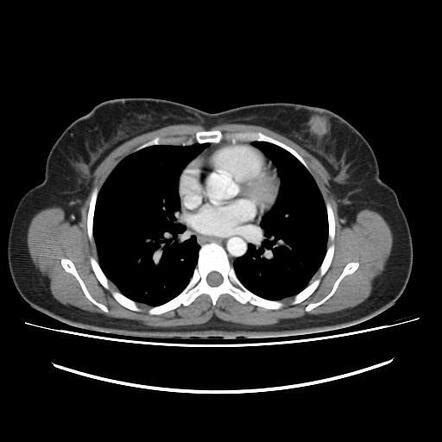

Getting a diagnosis can be a scary time, and understanding the process for diagnosing Triple-Negative Breast Cancer (TNBC) can help ease some of that anxiety. The journey usually starts with you noticing a change in your breast – maybe a lump, skin dimpling, nipple changes, or nipple discharge. If you spot anything unusual, the first step is always to see your doctor . They’ll perform a clinical breast exam and likely order imaging tests. The primary imaging tools are a mammogram and possibly an ultrasound or MRI , depending on your situation and breast density. These tests help visualize any abnormalities. If suspicious areas are found, the next crucial step is a biopsy . This is where a small sample of tissue is taken from the suspicious area, either with a needle or during a minor surgical procedure. The biopsy sample is sent to a lab where a pathologist examines the cells under a microscope. This is where the magic (and the crucial information) happens. The pathologist will determine if the cells are cancerous. If they are, they’ll then perform tests to see what kind of breast cancer it is. For TNBC, these tests are key. They’ll specifically look for the absence of estrogen receptors (ER) , progesterone receptors (PR) , and HER2 protein . If all three are negative, then you’ve got a TNBC diagnosis. It’s important to note that the initial biopsy might be tested for these markers, and sometimes further testing or a repeat biopsy might be needed for confirmation. Once diagnosed as TNBC, the medical team will also want to figure out the stage of the cancer . This involves seeing how large the tumor is and whether it has spread to nearby lymph nodes or other parts of the body. This is usually done through imaging like CT scans, bone scans, or PET scans. Staging is super important because it helps doctors determine the best treatment plan for you. Remember, while a TNBC diagnosis can feel daunting because of the treatment limitations, accurate and timely diagnosis is your best weapon. The medical team is there to guide you through every step, answer your questions, and develop a personalized treatment strategy. Don’t hesitate to ask for clarification on any part of the process; being informed empowers you.